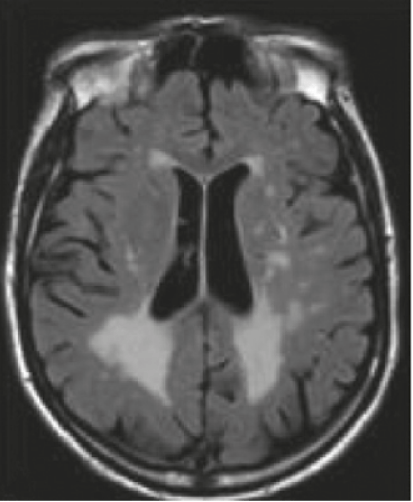

This image demonstrates an MRI of a 53-year-old male with Fabry disease showing cerebral white matter hyperintensities.

Fluid-attenuated inversion recovery (FLAIR)-weighted axial MRI section

Image reproduced with permission from Germain DP et al., 2010.1